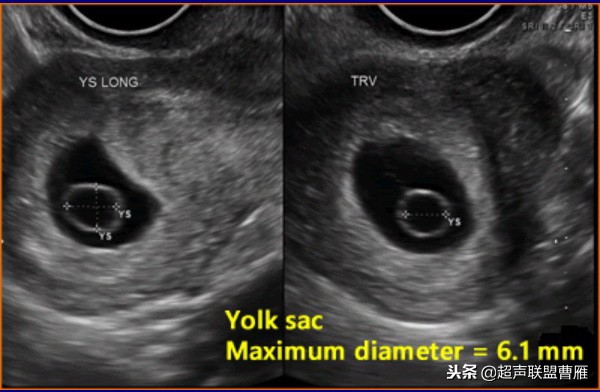

有的文献将卵黄囊内径的最大限度定为6.1mm

卵黄囊的大小与形态异常与胚胎的发育是否正常关系密切。卵黄囊增大,直径超过6.1cm,胚胎的预后不良。

卵黄囊的大小与形态异常与胚胎的发育是否正常关系密切。,形态异常的卵黄囊预后不良。

超声检查卵黄囊出现之后到孕龄12周之间多能见到卵黄囊,直径在0.3-0.5cm之间。卵黄囊的直径与形态正常是胚胎发育良好的标志。